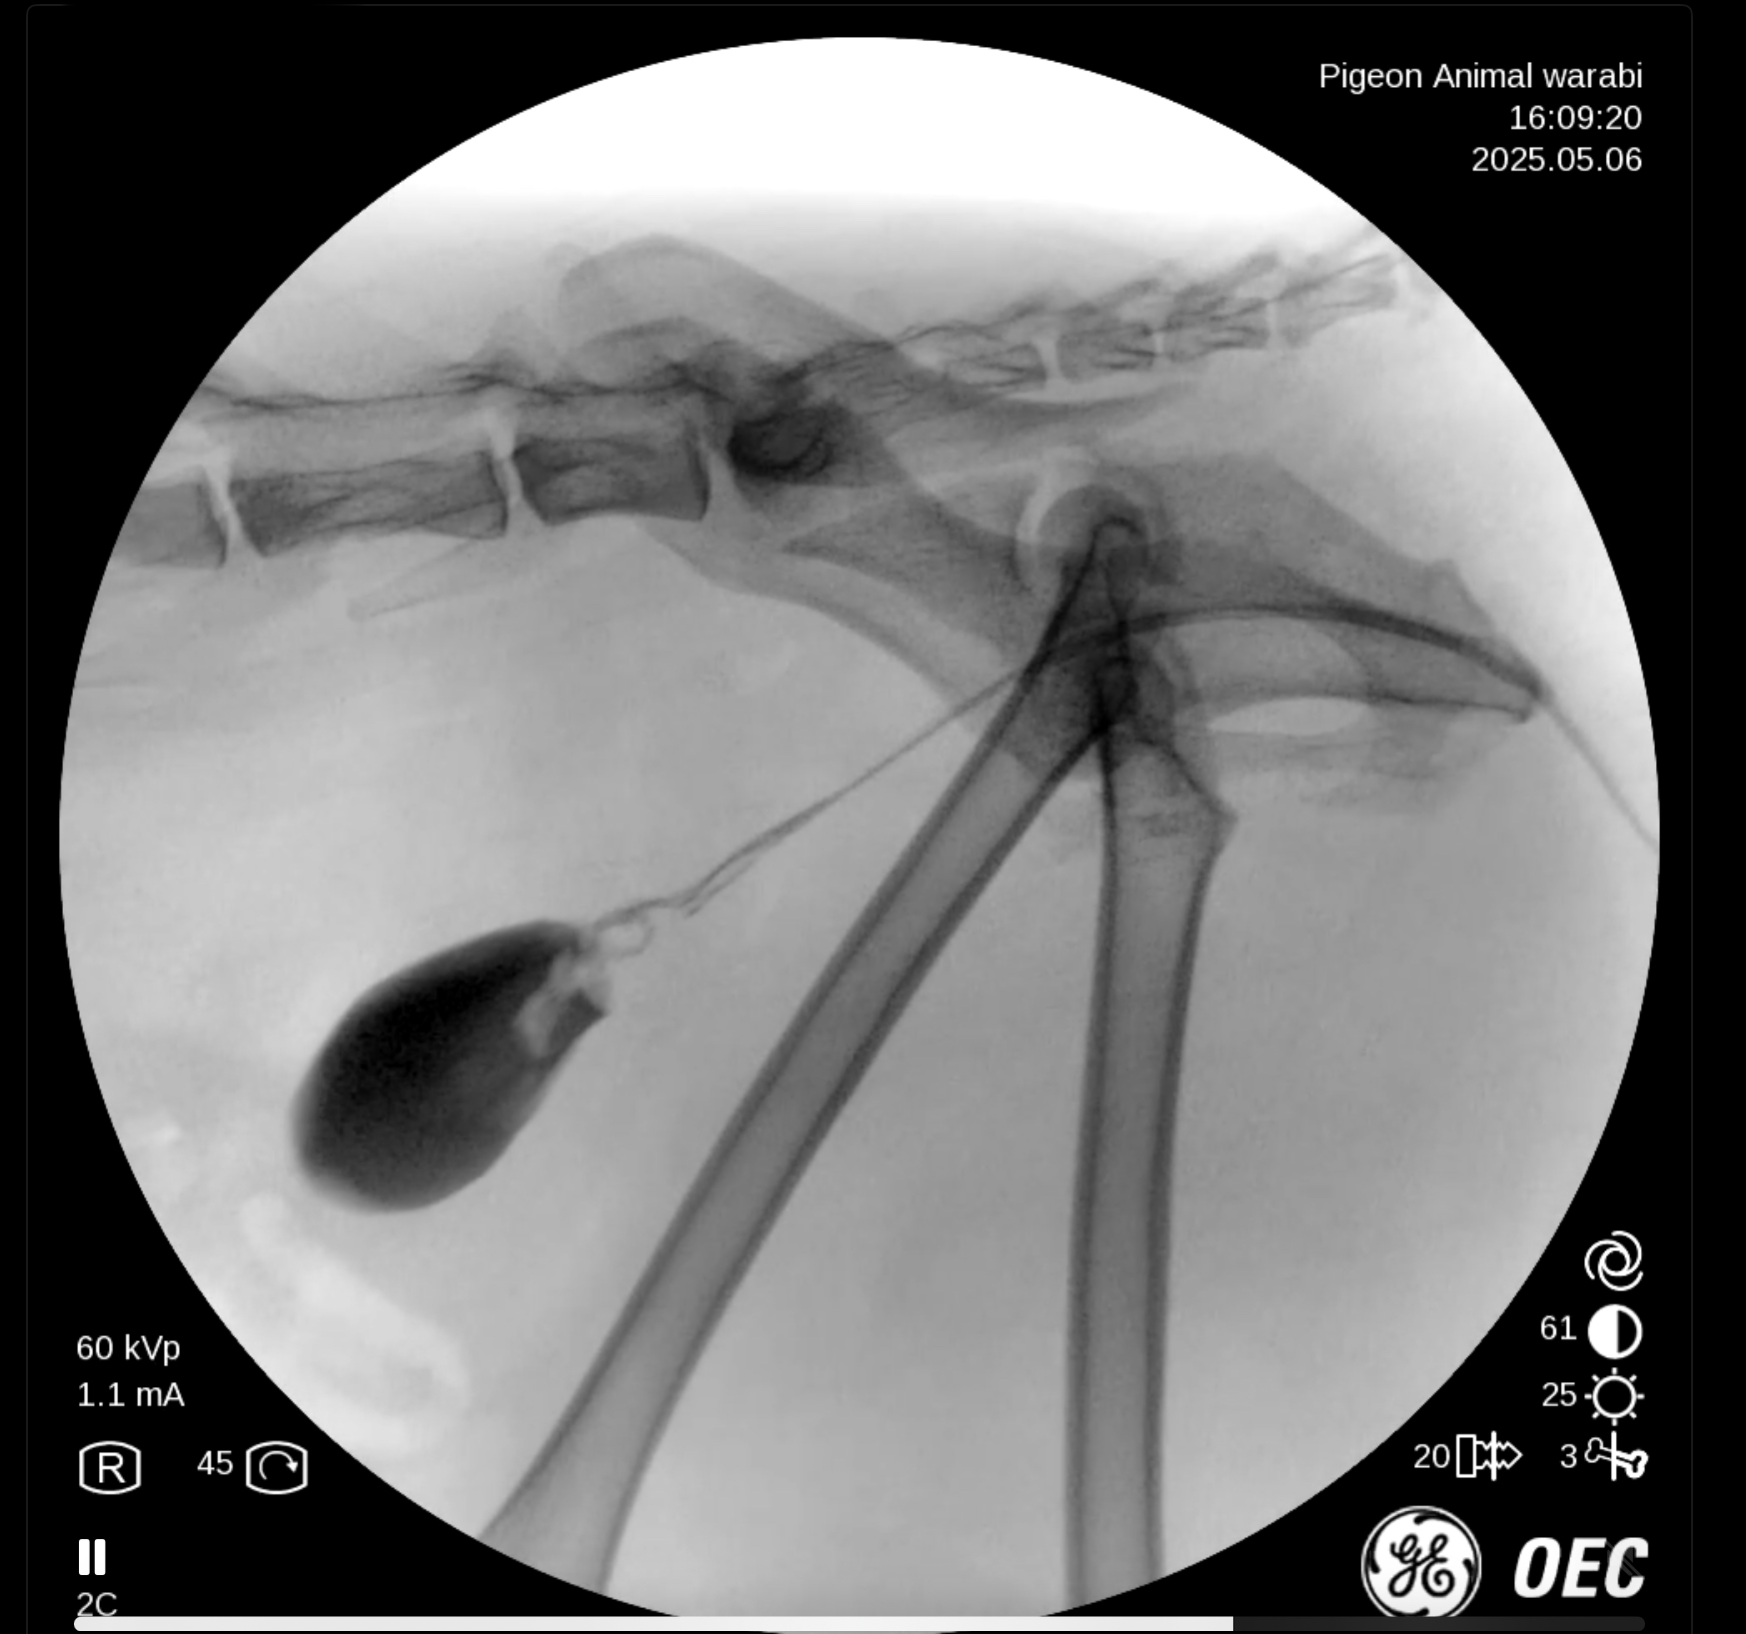

手術中の写真

膀胱、尿道の造影X線検査